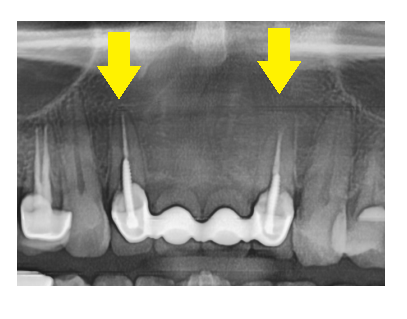

x-ray를 찍어보니 신경치료와 함께

기둥도 심어져있는게 확인됐는데요~

치아가 약해 보강한 증거입니다.

지금은 4개의 보철로 앞니가 연결되어있지만

상태가 안좋을 경우 6개로 치료해야한다